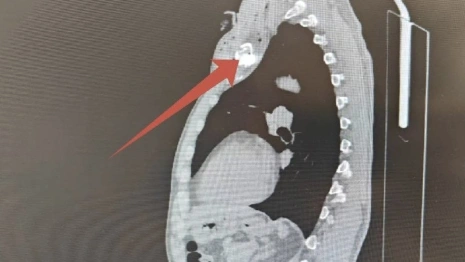

Врачи диагностировали Игорю непроникающее ранение в области ключицы, вколоченный перелом ключицы и инородное тело (осколок) в подключичной области. Состояние жизни не угрожает.